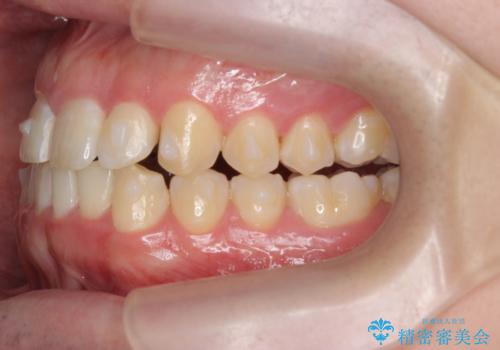

前歯が隠れていて見えない クロスバイトの矯正治療

- 「前歯が1本隠れていて見えない、歯並びを矯正治療で改善したい。」と希望され来院されました。

奥に隠れている前歯を並べられるスペースを確保したのち、歯並びを整えていきます。

前歯のスペース不足により1本だけ後方に位置している状態でしたが、しっかりとスペースを確保し配列することができました。